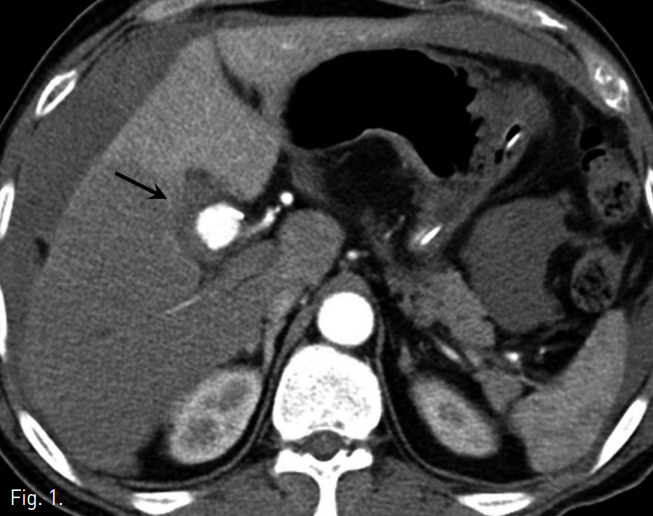

조영증강 복부 CT에서 우간동맥에 약 2cm 크기의 가성동맥류가 관찰됨(Fig. 1).

Fig. 1

Abdominal CT shows a pseudoaneurysm at right hepatic artery (arrow).